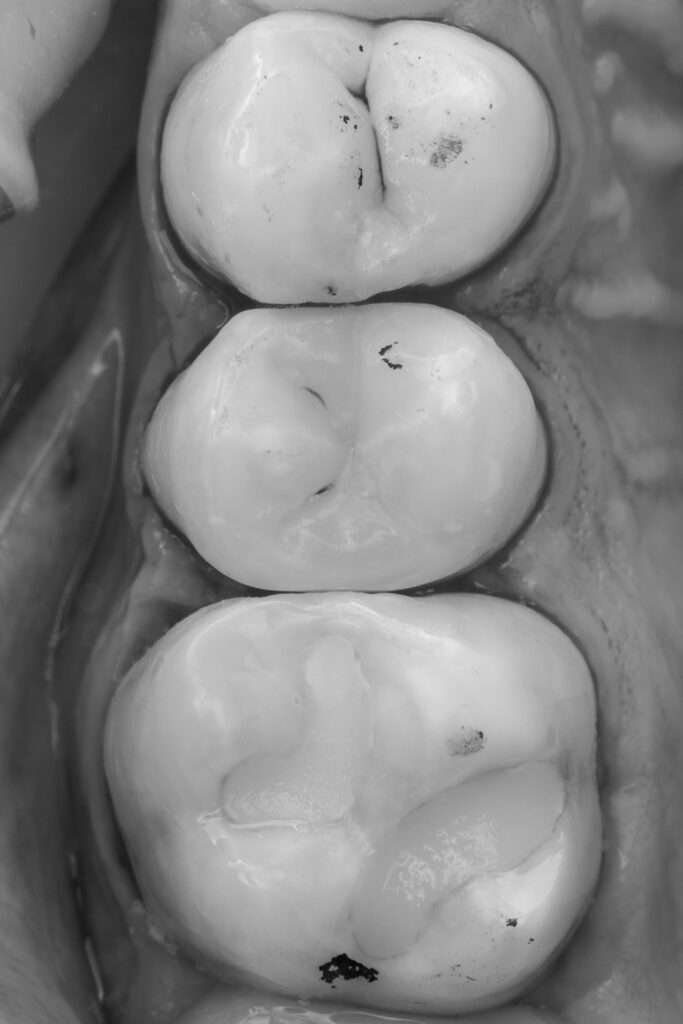

For restoration of the proximal walls, Asteria A3B composite resin was used.

EvoCeram Dentin 2 was applied as the dentin substitute.

Final anatomical contouring of the tooth was performed using NeoSpectrum A2 composite resin.